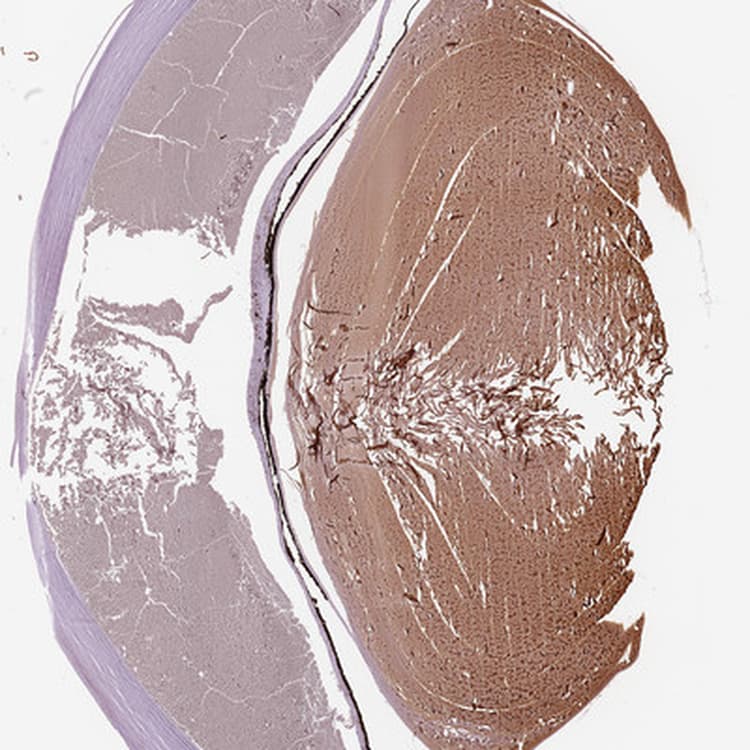

Anti-Filensin antibody(ab251869)

Rabbit Polyclonal Filensin antibody. Suitable for IHC-P, WB, ICC/IF and reacts with Human samples. Immunogen corresponding to Recombinant Fragment Protein within Human BFSP1 aa 250-350.